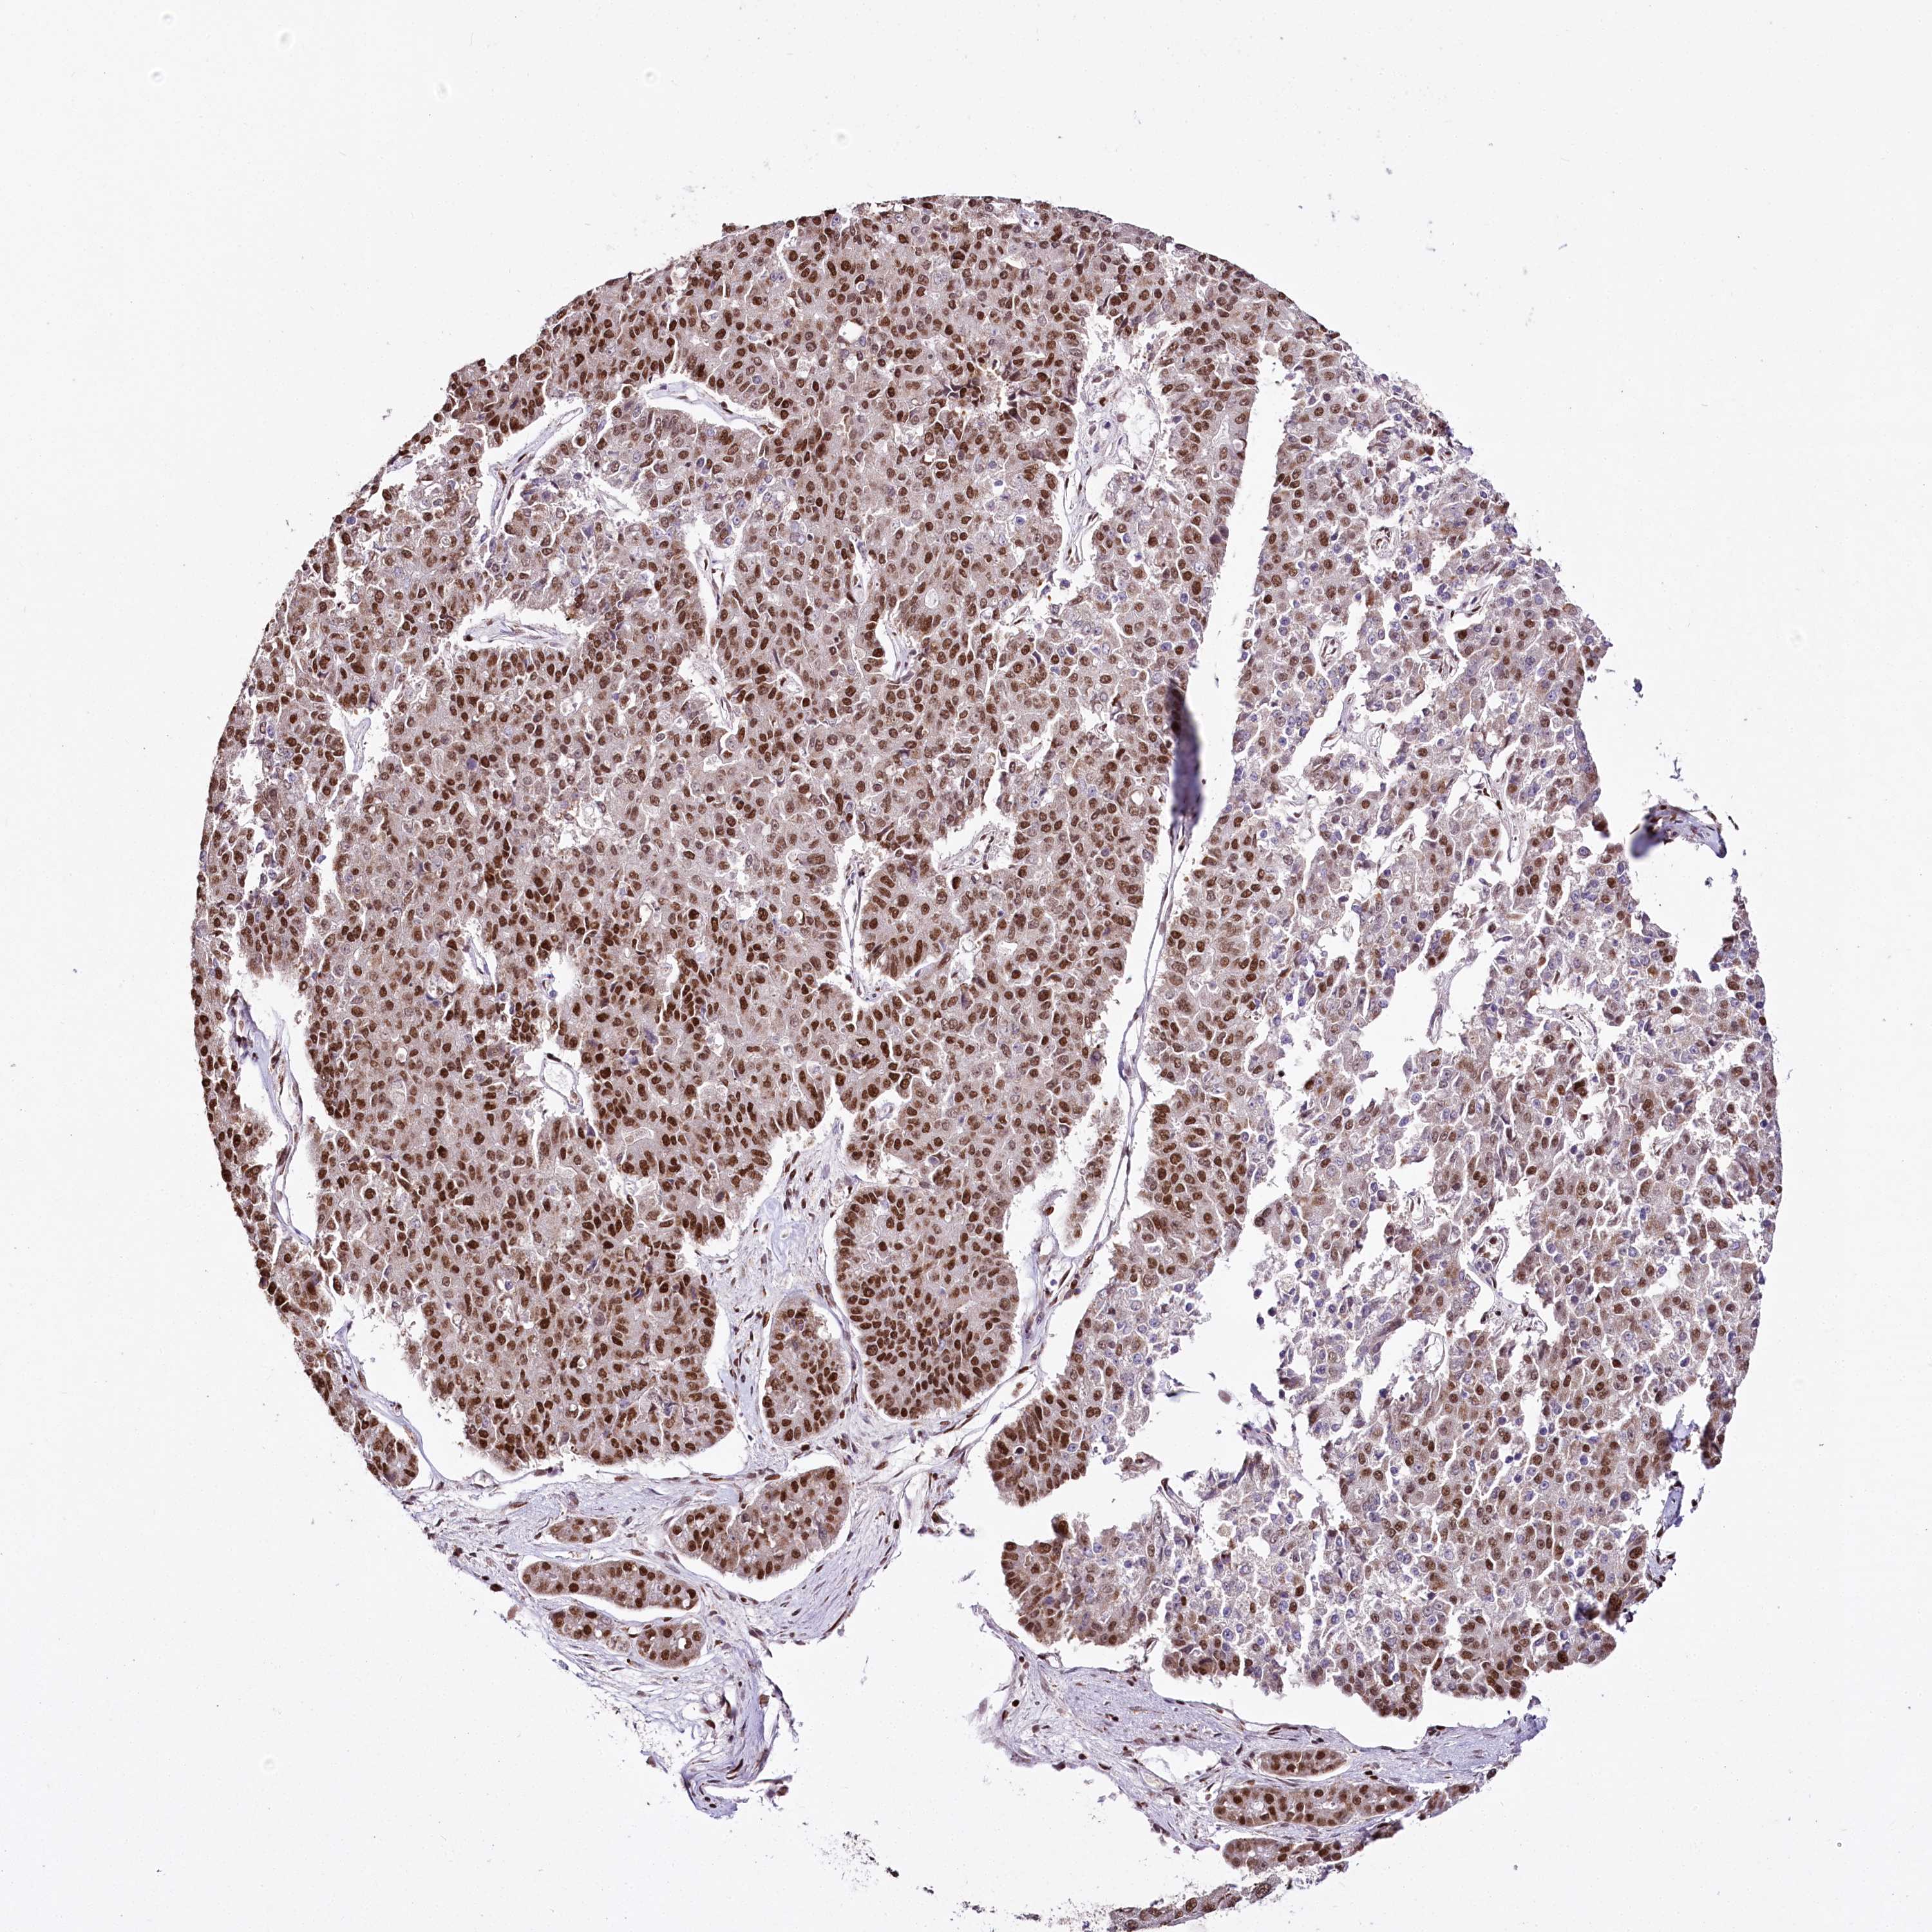

PANCREATIC CANCER - Protein expressioni

A mouse-over function shows sample information and annotation data. Click on an image to view it in a full screen mode. Samples can be filtered based on level of antibody staining by selecting one or several of the following categories: high, medium, low and not detected. The assay and annotation is described here.

Note that samples used for immunohistochemistry by the Human Protein Atlas do not correspond to samples in the TCGA dataset.

Antibody stainingi

Antibody staining in the annotated cell types in the current human tissue is reported as not detected, low, medium, or high, based on conventional immunohistochemistry profiling in selected tissues. This score is based on the combination of the staining intensity and fraction of stained cells.

Each image is clickable and will lead to virtual microscopy that enables deeper exploration of all samples and also displays staining intensity scores, fraction scores and subcellular localization as well as patient and tissue information for each sample.

Antibody HPA003916

Antibody CAB037318

Staining

High

Medium

Low

Not detected

Intensity

Strong

Moderate

Weak

Negative

Quantity

>75%

75%-25%

<25%

None

Location

Nuclear

Cytoplasmic/membranous

Cytoplasmic/membranous,nuclear

Adenocarcinoma, NOS

Adenocarcinoma, metastatic, NOS